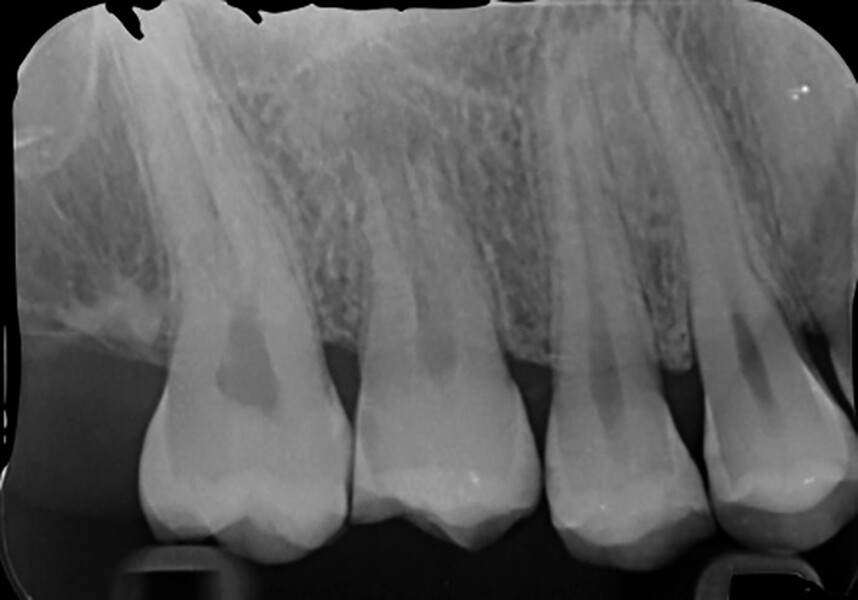

Fig. 16b: Radiograph at the one-year recall.

Fig. 16c: Radiograph at the 11-year recall.